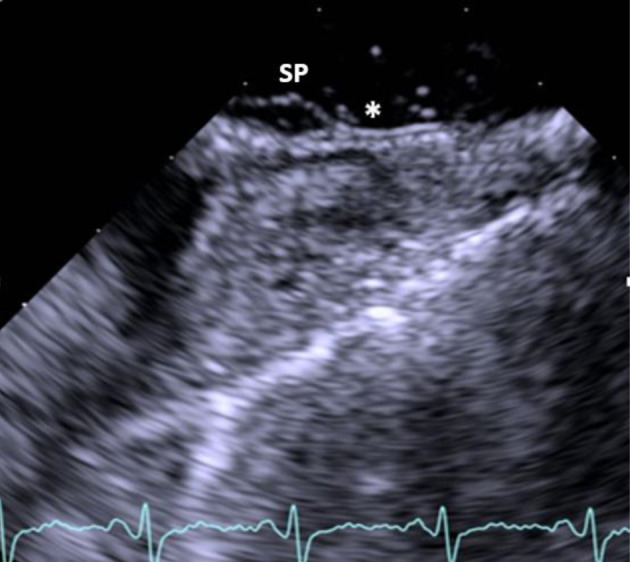

双房间隔(DIAS)现象是一种特别罕见的房间隔畸形亚型,其特点是存在双膜将心房分隔开来,形成一个独特的心房间隙。这种独特的解剖结构与矛盾性右向左分流有关,可能导致栓塞性缺血性脑卒中。在此背景下,我们报告了一例罕见病例,患者是一名 34 岁女性,突发短暂性脑缺血发作(TIA),被诊断为卵圆孔未闭(PFO)和邻近的一个小的房间隔缺损(ASD),并伴有 DIAS。经食道超声心动图和心脏磁共振成像(MRI)证实了这一诊断,并使用经导管封堵器成功治疗了该病。

The phenomenon of double interatrial septum (DIAS) represents a particularly rare subtype of atrial septal malformation, characterized by the presence of dual membranes separating the atria, resulting in a distinctive interatrial space. This unique anatomical structure has been linked to a paradoxical right-to-left shunt, potentially contributing to embolic ischemic strokes. Within this context, we report a rare case of a 34-year-old female who presented with a transient ischemic attack (TIA) and was diagnosed with patent foramen ovale (PFO) and a small adjacent atrial septal defect (ASD), along with the presence of a DIAS. The diagnosis was confirmed wit transoesophageal echocardiography and cardiac magnetic resonance imaging (MRI), and the condition was successfully treated with a transcatheter occluder device.